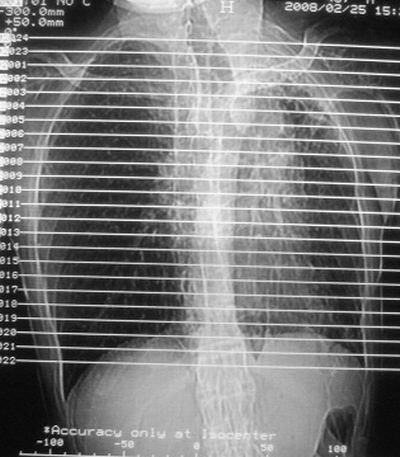

患者,男,47岁,反复咳嗽、咯痰、咯血3年,再发5天。痰培养未找到真菌、抗酸杆菌、癌细胞。

胸片上看很像“垂柳征”,支持肺结核!左下肺炎症!还有肺气肿!

左肺上叶体积明显缩小,其内见多发透光区,纵隔向左侧移位,左肺下叶多发班片状病灶,边界模糊,1左肺上叶先天肺发育不全,2左肺下叶肺炎,

左肺上叶结核伴肺纤维化,纵隔移位,左肺下叶感染性病变,建议抗炎抗结核后复查,双肺气肿.

左肺上叶体积明显缩小,其内见多发透光区,纵隔向左侧移位,左肺下叶多发班片状病灶,边界模糊,1左肺上叶先天肺发育不全

以下是引用xulianj在2008-2-25 21:01:00的发言:[br]左肺上叶结核伴肺纤维化有霉菌球形成,纵隔移位,左肺下叶感染性病变,建议抗炎抗结核后复查,双肺气肿.

考虑:左肺慢纤伴霉菌球形成、双肺全小叶型肺气肿。

1)考虑为:左肺上叶肺结核(空洞形成),伴左下肺感染;不排除霉菌感染可能。2)肺气肿。

左肺上叶结核伴肺纤维化空洞形成并左肺下叶感染,纵隔牵拉移位,建议作进一步检查排除左侧肺霉菌感染可能。